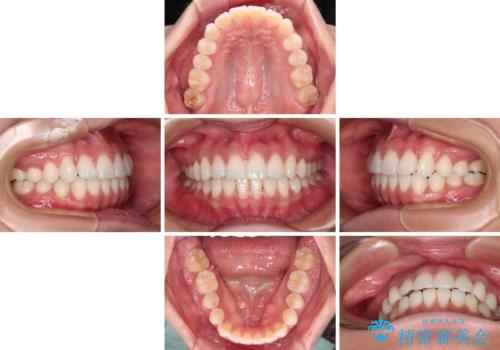

【モニター】インビザラインで口を閉じやすく

- 20代女性

- インビザライン

- 9ヶ月

- 前に出ている上顎前歯が気になるとのことで来院された患者様です。

インビザラインを用い、IPR(歯と歯の間を削る)と歯列全体を後方に移動させることで、可能な限り前歯の突出感を改善することとしました。

元々の歯列も整っており、横顔の印象の出っ歯ではなかったため、仕上がりに満足できない可能性があると心配しておりましたが、口が閉じやすくなり、患者様には大変満足していただきました。